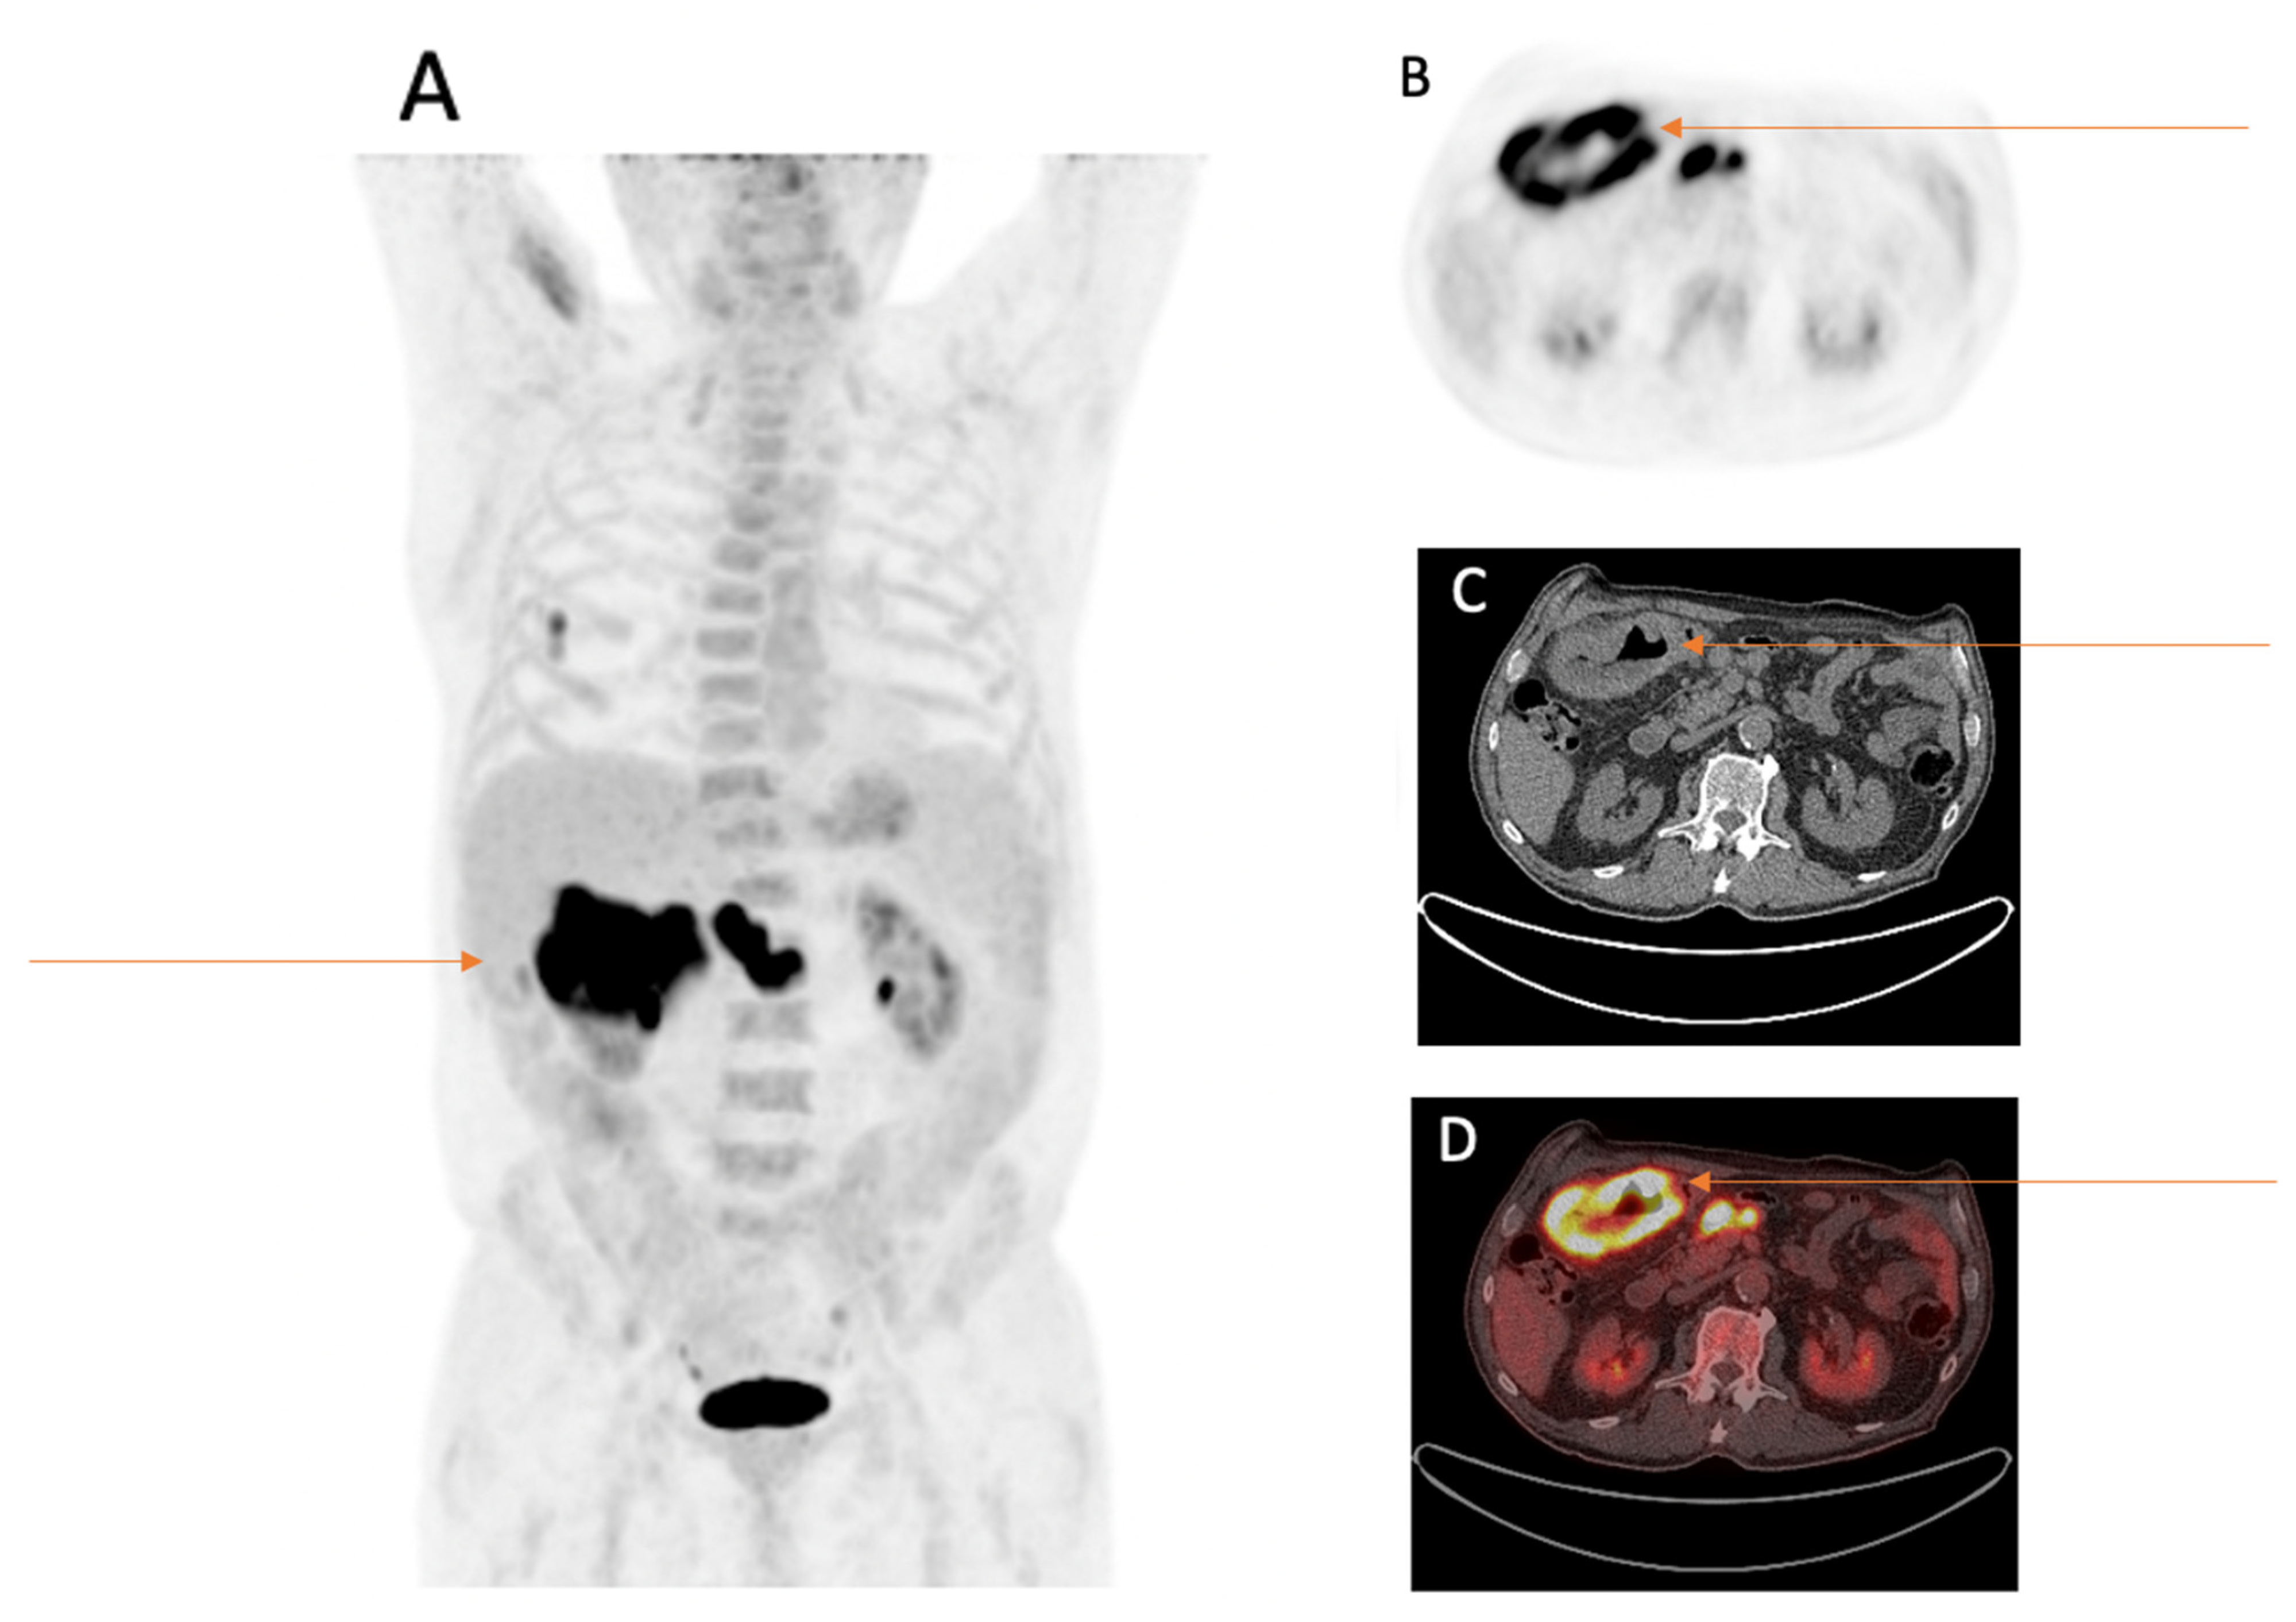

Figure 3.

Eighty-three-year-old male patient with first diagnosis of NSCLC (TTF1 positive adenocarcinoma of the right lower lobe pT1b, pN0, M0) underwent FDG-PET/CT for staging. FDG-PET/CT scan displayed an incidental FDG-avid wall thickening of the right colon flexure with three FDG-avid locoregional lymph nodes. (A) MIP image after the intravenous injection of 322 MBq 18F-FDG. (B) PET image of the right colon flexure. (C) CT image of the right colon flexure. (D) Fused PET/CT image of the right colon flexure. After further investigations, the wall thickening was histopathologically confirmed as microsatellite stable adenocarcinoma of the colon ascendens pT3 N2a (4/26), V1, L1, R0.